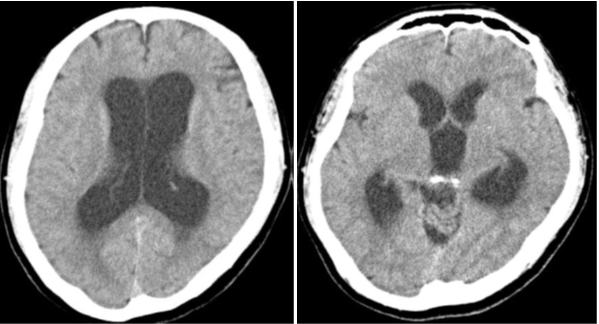

Figure 4 Postoperative computed tomography showed improvement in ventriculomegaly.

A 52-year-old man with a headache and consciousness disturbance was taken to our hospital by ambulance. He had a history of thrombocythemia and was taking aspirin. At the time of the visit, his consciousness was GCSE4V4M6, and displayed an upward gaze disorder. Computed tomography (CT) at the first visit revealed ventricular enlargement and a cyst with calcification in the pineal gland. Additionally, ventricular enlargement was visible on MRI, and a pineal gland cystic lesion with a wall thickness of 15 mm was discovered. The signal inside the cyst was lower than that of the surrounding brain parenchyma and higher than that of the cerebrospinal fluid. The cyst wall was thin and smooth, and no septal structure or nodules were discovered inside, so we diagnosed a pineal cyst. The operation was performed under general anesthesia, trepanned on the right frontal mid-pupillary line and in front of the coronal suture, and a transparent sheath was placed and a flexible scope was inserted. The cerebral aqueduct intermittently became blocked as the cyst floated in time with the cerebrospinal fluid flow. With forceps, the cyst wall was ruptured, releasing a fluid with a pale yellowish serous content. When about half of the cyst wall was removed, it was validated that the cyst had originated from the pineal gland, and the cerebral aqueduct became observable, so we decided to finish the cyst wall removal. Furthermore, we conducted an endoscopic third ventriculostomy, and pulsatile movement of the third ventricular floor was observed. The operation improved the ocular motility disorder and consciousness disorder, and the ventricles shrank on CT. Postoperative MRI revealed that the cyst wall was discontinuous, and the stoma of the third ventricle was also verified. After the surgery, the postoperative course was uneventful and he was discharged on the 8th postoperative day without complications. Ventriculomegaly was not found. on MRI six months after the operation.